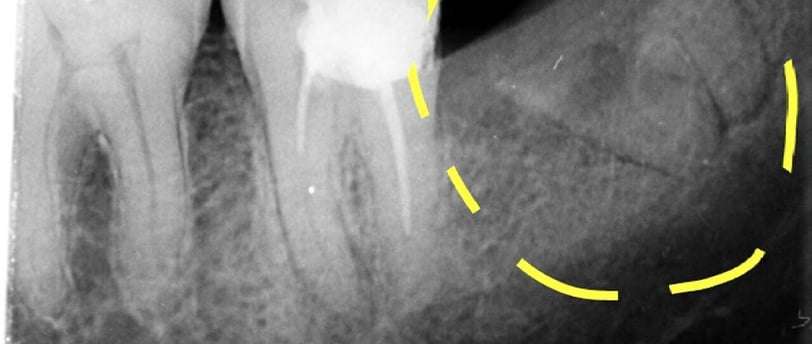

Radiografiile retroalveolare sunt concepute pentru a oferi imagini detaliate ale regiunii alveolare, care conține rădăcinile dinților și structurile osoase adiacente. Aceste radiografii se realizează în principal pentru a evalua sănătatea rădăcinilor dentare și pentru a detecta eventuale afecțiuni sau probleme din acest domeniu.

Evaluarea rădăcinilor dentare: Aceste radiografii sunt esențiale pentru evaluarea stării rădăcinilor dentare, identificarea leziunilor sau a altor probleme legate de rădăcini.

Identificarea afecțiunilor osoase: Aceste radiografii pot ajuta la identificarea afecțiunilor sau a problemelor osoase din regiunea alveolară.

Diagnosticul leziunilor endodontice: Aceste radiografii sunt esențiale în diagnosticul afecțiunilor pulpare și pentru ghidarea tratamentelor endodontice.

Evaluarea rădăcinilor dinților: Radiografiile retroalveolare ajută la evaluarea stării rădăcinilor dentare și la detectarea eventualelor anomalii.